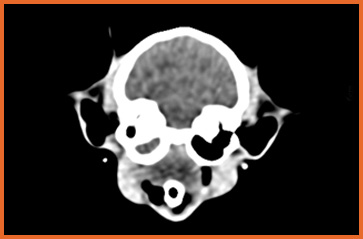

我們提供留院服務並擁有相應的治療設施,亦是小數備有CT電腦掃描及MRI磁力共振等大型醫療儀器的診所及醫院。